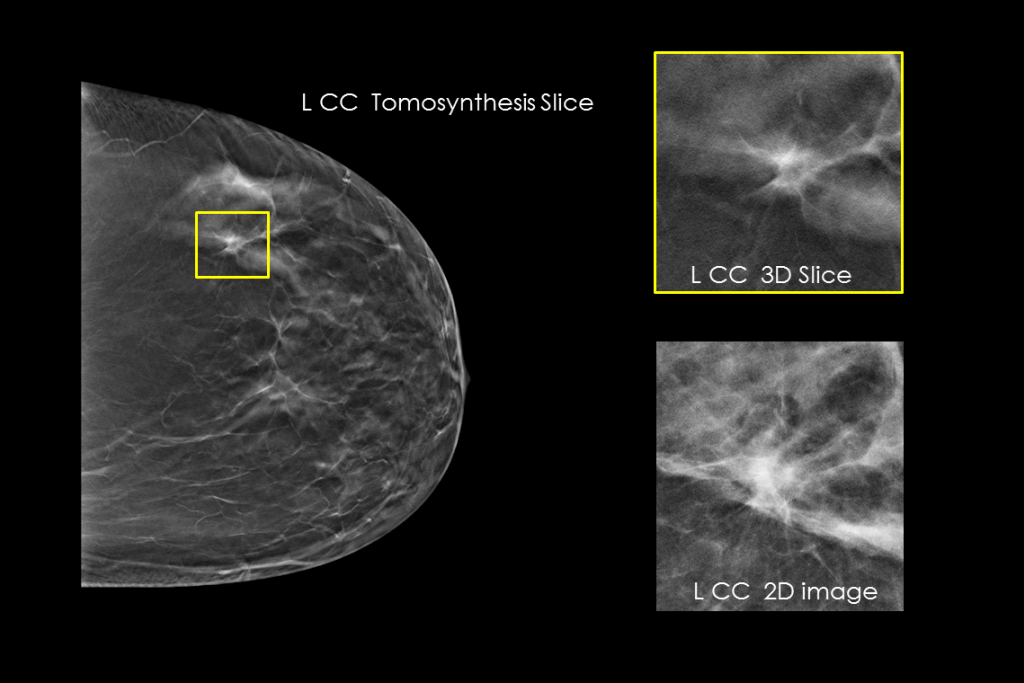

Klinische beelden van borstscan met verdachte laesie